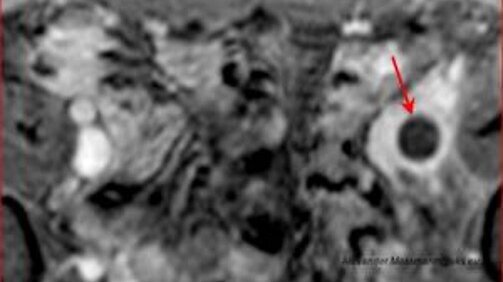

Hier ist das verschlossene Gefäß, in diesem Fall die Beckenvene (Vena iliaca), im Querschnitt zu sehen (mit Pfeil markierter schwarzer Kreis). Das Blutgerinnsel füllt die Vene vollständig aus.